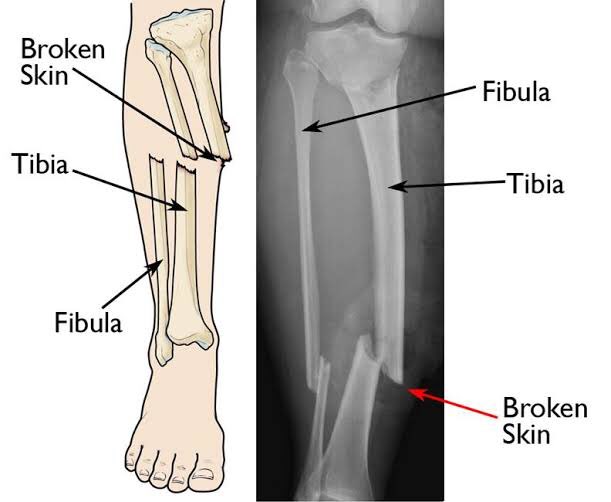

٦- الكسر

اعراض الكسر وجع شديد و احمرار فمنطقة الكسر عدم القدرة عالحركة الا فكسور معينة الشخص يعرف يتحرك عليها عادي بس خطر طبعا الاستمرار عليها

طب تتصرف ازاي؟